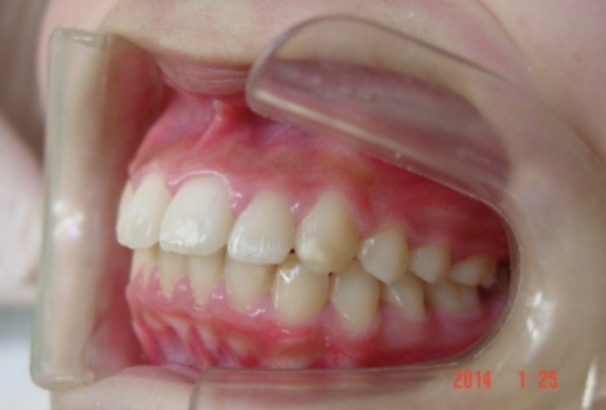

Before

| 症状 | 上顎前歯の右側転位のために、右側2番の舌側転位と右側3番(犬歯)の萌出スペースなし。 |

| 通院時の 年齢 |

10歳2か月 |

| 通院目的 | 永久歯を抜かずに治したい。右上の八重歯が気になる。 |

| 処置内容 | 1期治療 プレート拡大装置 2期治療 マルチブラケット装置(右上7番抜歯してそこに右上8番親知らずを誘導した。) |

| デメリット・院長コメント | 永久歯を抜かない治療のデメリットは、治療期間が長いことです。ただし、その後の人生の長さを考えると、健全な小臼歯を2本または4本抜歯の矯正治療よりも、はるかにメリットがあるといえます。また、アーチが小さくならないので、舌が後ろに押し込まれないためいびき防止につながり睡眠の質の向上にもつながります。 |